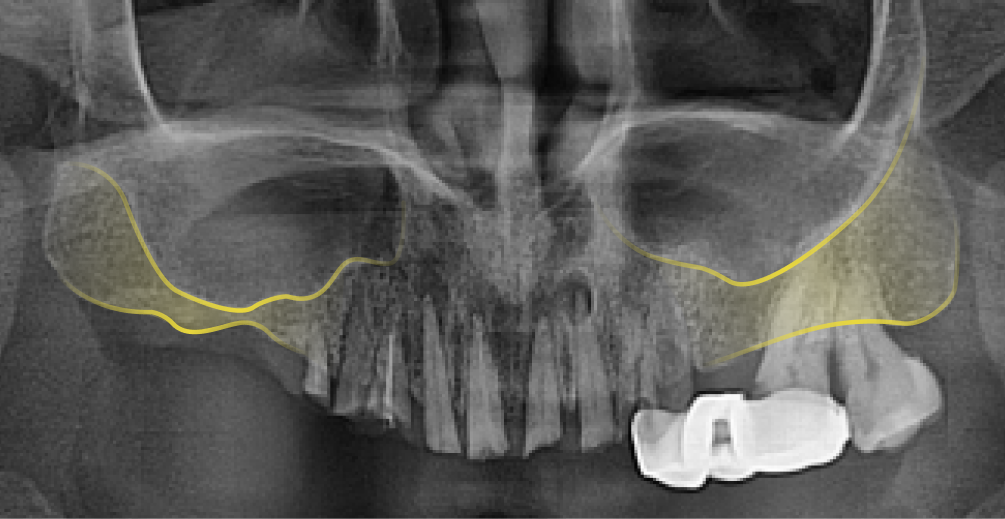

상악동(위턱뼈 속의 비어있는 공간)거상술은 상악동과 잇몸뼈 사이에 임플란트를 심을 수 있는 만큼의 충분한 뼈가 존재하지 않을 때, 그 공간을 살짝 들어 올려서 잇몸뼈를 채워 넣는 시술 을 말합니다.

상악동은 원래 팽창하려는 성질이 있어 치아가 빠진 이후 오랜 시간 방치했거나 나이가 들면서 치조골이 약해지면 상악동이 아래로 내려오면서 커지는 증상이 발생합니다. 이를 상악동의 함기화(Sinus Pneumatization) 라고 하며, 상악동이 아래로 내려오면서 임플란트 식립이 어려울 만큼 뼈가 얇아지게 됩니다. 이렇게 뼈가 얇아져 임플란트 식립이 어려울 때, 상악동을 위로 들어 올려 뼈를 이식하는 ‘상악동 거상술(Sinus Lift , Sinus Elevation)’을 진행합니다.

• 상악동 거상술 전

상악동 거상술 전, 얇은 잇몸뼈

• 상악동 거상술 후

상악동 거상술 후, 두꺼워진 잇몸뼈

*노란선 : 잇몸뼈와 상악동의 경계선 *파란선 : 상악동 거상술 이후 잇몸뼈와 상악동의 경계선

상악동은 아래턱에 비해 밀도가 낮고, 두껍지 않아서 찢어지거나 구멍이 생길 수 있는 위험이 있는 고난이도 수술이기 때문에 의료진의 경험과 시술 노하우, 그리고 안전한 장비를 갖춘 치과에서 시술받아야 합니다.